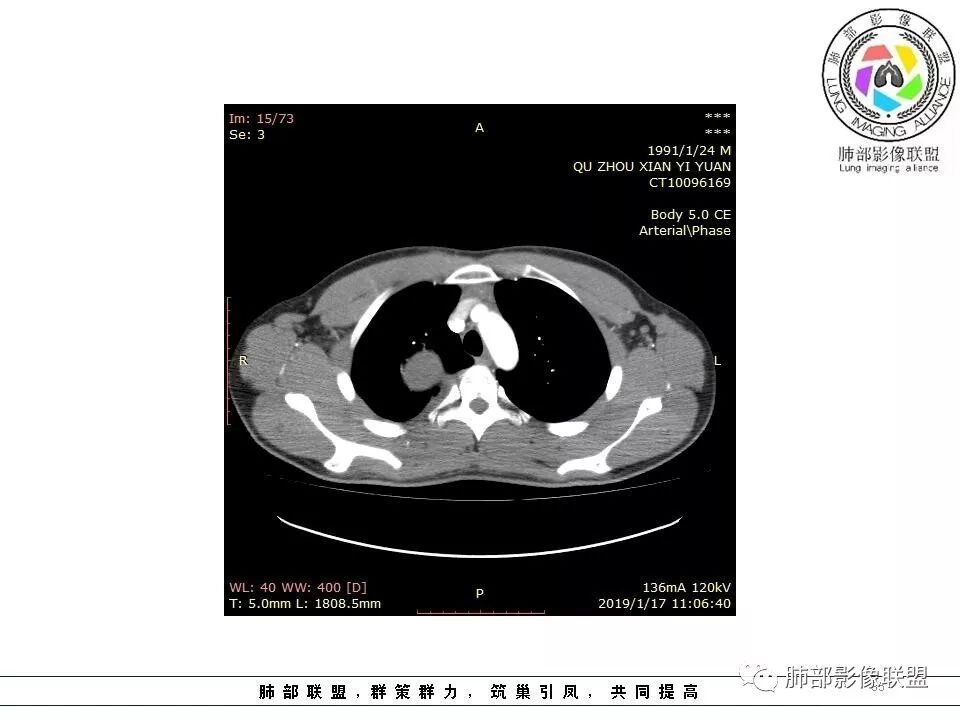

右后纵膈脊柱旁软组织占位,形态规则类圆,边缘光整,肺组织受压,胸膜尾,肋间动脉供血。中度不均匀延迟强化。

右后纵膈脊柱旁软组织占位,边界清晰,光整,肺组织受压。胸膜被掀起,肋间动脉供血,中度不均匀延迟强化。考虑神经鞘瘤,不除外纤维瘤

右后纵膈脊柱旁软组织影,与纵隔结构分界不清,形态规则类圆,边缘光整,肺组织受压,胸膜尾,肋间动脉供血。肺动脉推移,中度不均匀延迟强化。考虑神经来源,神经鞘瘤,神经纤维瘤二者不易鉴别。

青年男性,间断胸痛;右侧脊柱旁可见一类圆形软组织密度影,密度欠均匀,增强扫描呈轻中度持续强化,邻近肺组织及肺动脉推移,可见肋间动脉供血,部分胸膜下脂肪可见,部分层面似见与右侧椎间孔相连。考虑后纵隔神经源性肿瘤。

青年男性,间断胸痛。右后纵膈脊柱旁软组织占位,形态规则类圆,边缘光整,肺组织受压,D字征,胸膜尾,肋间动脉供血。中度不均匀延迟强化。无支气管进入考虑来源于肺外、肿块与脊柱间未见明显脂肪间隙,考虑来源于胸膜外,考虑神经源性肿瘤,建议穿刺活检。

1.右上胸内脊柱旁类圆形肿块,质地似乎比较坚实,密度稍显不均,但未显示明确的坏死。

如此密度形态的病灶位于肺边缘首先应当想到孤立性纤维瘤,可相邻胸膜未见明显的异常强化和胸膜方向延伸。

2.肋间动脉病供血也提示肿块来自后纵隔?